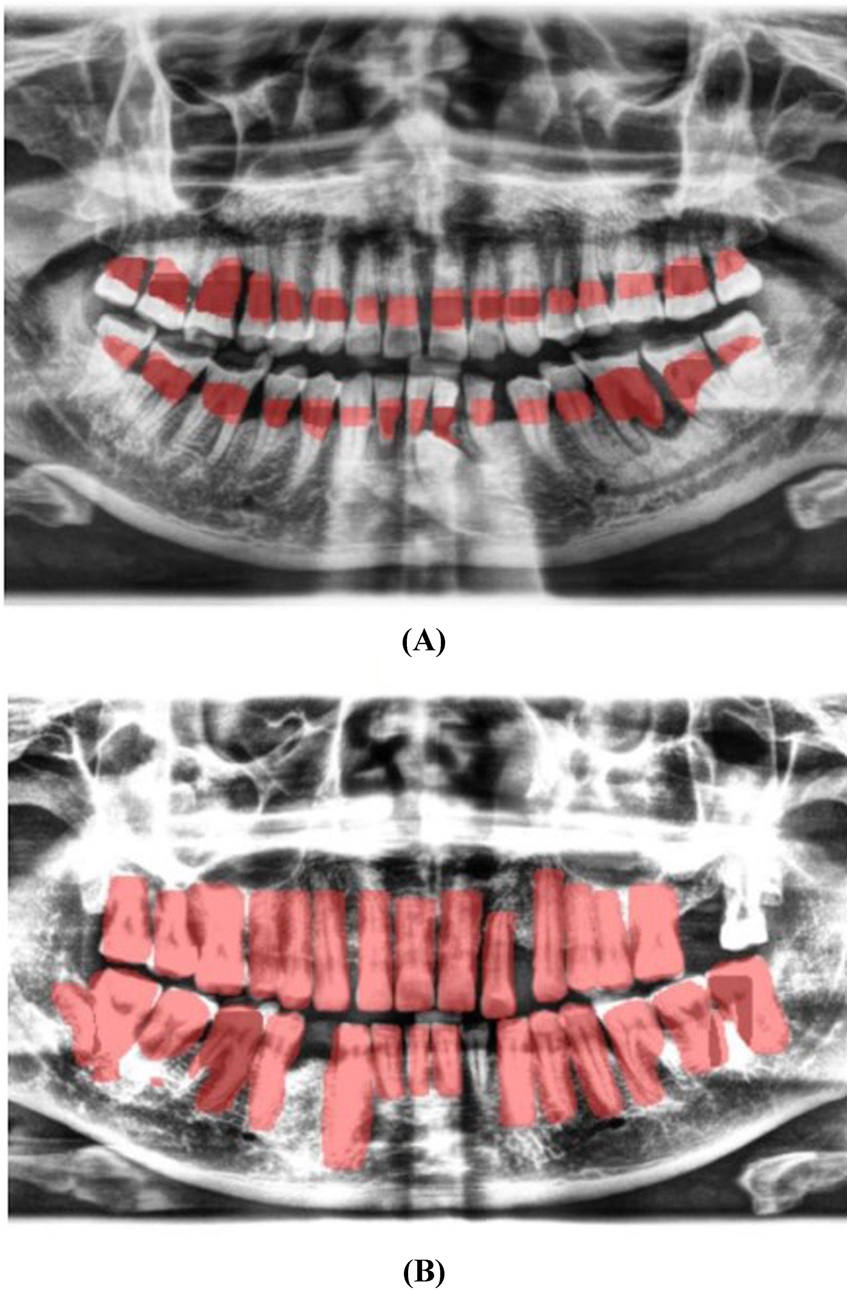

Localization and Classification: The model was trained to identify and localize the region between the cemento-enamel junction (CEJ) and the alveolar bone crest, producing bounding boxes or heat maps for further analysis (Figure 5).

- 4.Thresholding for Abnormality Detection (Severity of Periodontitis):

A thresholding mechanism will be devised to determine the extent of abnormality based on the width of the gap between the CEJ and the bone structure (

Figure 6). Teeth with gaps exceeding the predefined threshold (e.g., >2 mm) will be flagged as abnormally positioned. To calculate the percentage of bone loss, use the formula (

18):

For periodontal diagnosis, the assessments involved calculating the percentage of alveolar bone loss for each tooth in the radiographs. The stage of periodontitis for each patient was determined based on the greatest bone loss observed across all teeth, which was then used to assign the appropriate periodontitis stage as follows (

Figure 7):

- •

Stage I: Bone loss of less than 15% visible in x-rays.

Stage II: Bone loss ranging between 15% and 33% visible in x-rays.

Stage III: Bone loss extending beyond the middle third of the root, with up to 20 teeth remaining.

Stage IV: Similar to Stage III, with bone loss extending beyond the middle third of the root, but with fewer than 20 teeth remaining.

Figure 5

Image showing the predicted area between the CEJ and the alveolar bone crest (A), and teeth segmentation (B).